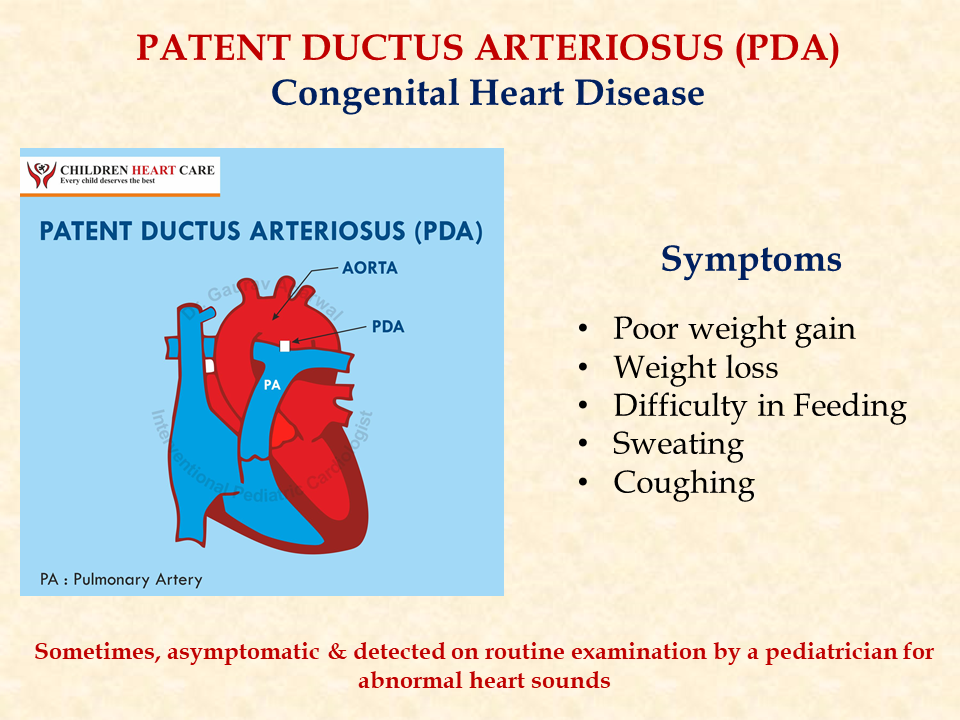

PDA Pathophysiology and Anatomy

Morphology of the PDA in premature infants The PDA resembles a hockey

PATENT DUCTUS ARTERIOSUS PDA IN CHILDREN Dr Gaurav Agrawal

Patent Ductus Arteriosus PDA in the newborn

PDA morphology and size are extremely variable in premature babies